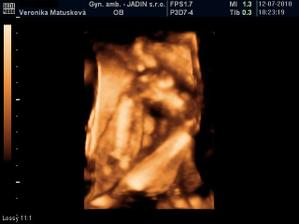

Adamko - 3D/4D

No tot vidno, že je náš syn, sa hanbil a hanbil až sa ukazovať nechcel....ale niekedy sa to podarilo, aj ked to nie je nejaká sláva. Pán doktor nám potvrdil chlapčeka, tak sme radi, vajká ukazoval ako len vedel len toho pipíka stále schovával. Ale je to za nami, pán doktor nás pekne popísal čo je kde, poodmeral nás a povedal, že je všetko v poriadku.